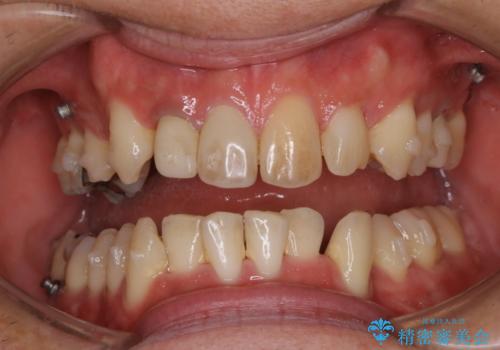

- ご自身の歯の色を、今より白くしたいと希望されたので一日で白くなるオフィスホワイトニング(エクセレント)をおすすめしました。

オフィスホワイトニング(エクセレント)

歯の色が自然な感じに白くなり、きれいになったと満足していただけました。